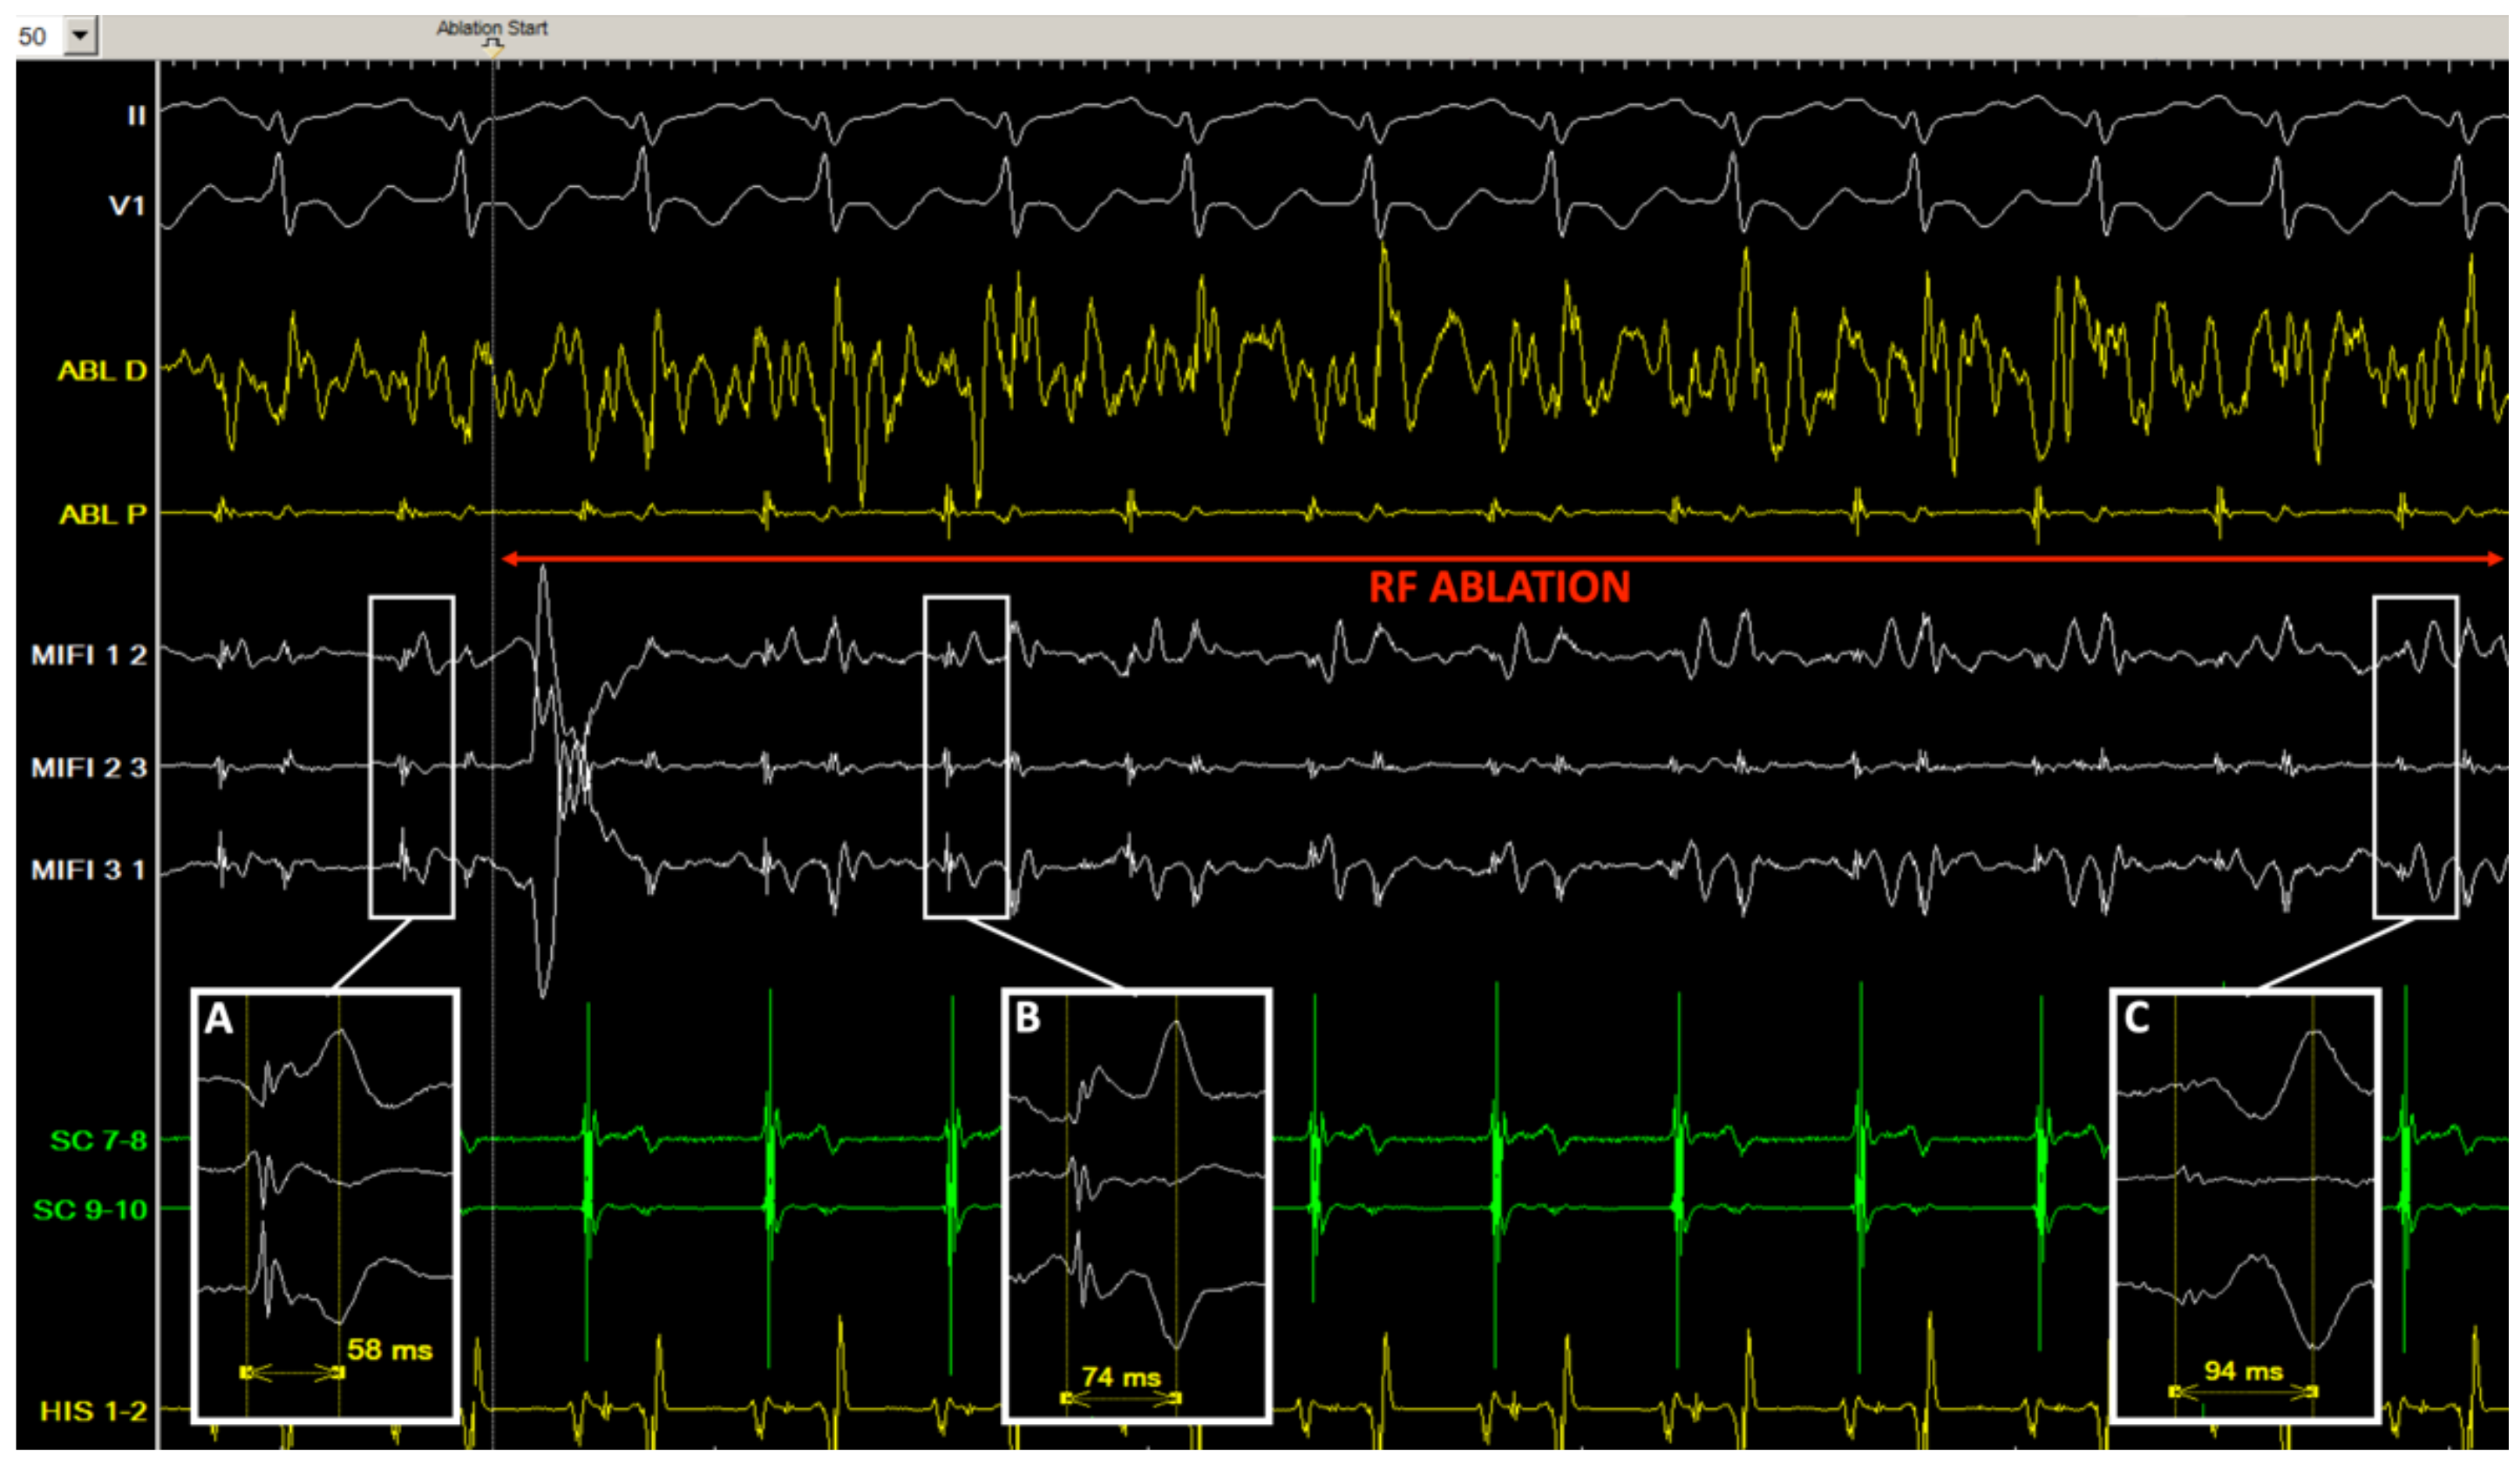

3.5. Double Potentials